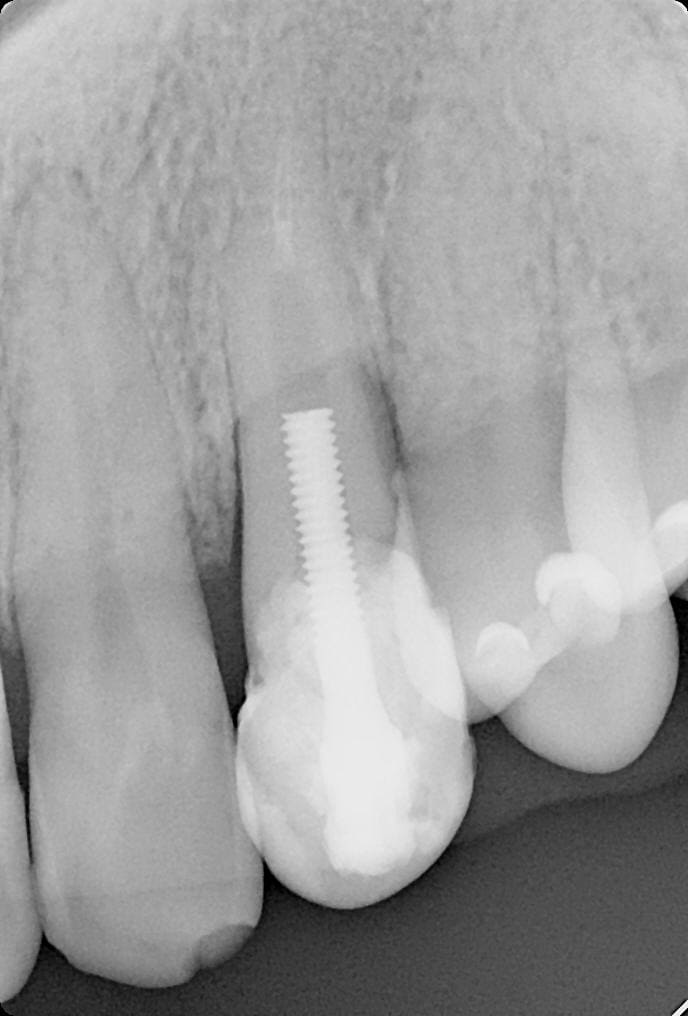

identification implant

CT

question subsidiaire , fracture ou pas fracture?

https://www.castorama.fr/tige-filetee-brillante-zinguee-diametre-3-mm-x-1-m/3663602754404_CAFR.prd